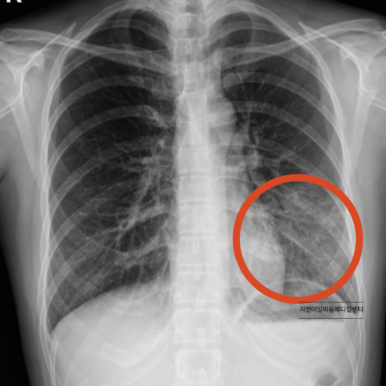

기침 증상으로 내원하셔서 폐렴이 발견된 사례

정상적인 심장 기능은 폐와 전신으로 원활한 혈류를 공급합니다. 하지만 심장 기능이 저하되면 특히 좌심실의 펌프력이 약해지면서 폐에 혈액이 정체되게 됩니다. 이를 폐울혈이라고 하며, 폐 속의 모세혈관과 조직에 과도한 압력이 가해져 체액이 새어 나오게 됩니다.

이러한 울혈과 조직 부종은 폐의 기침 수용체(J-receptor)를 자극하게 되고, 이로 인해 마른기침 또는 숨이 찬 증상이 발생합니다. 더 진행되면 폐포까지 물이 차는 폐부종으로 이어져, 기침은 더욱 심해지고 분홍빛 거품 가래가 동반되기도 합니다.